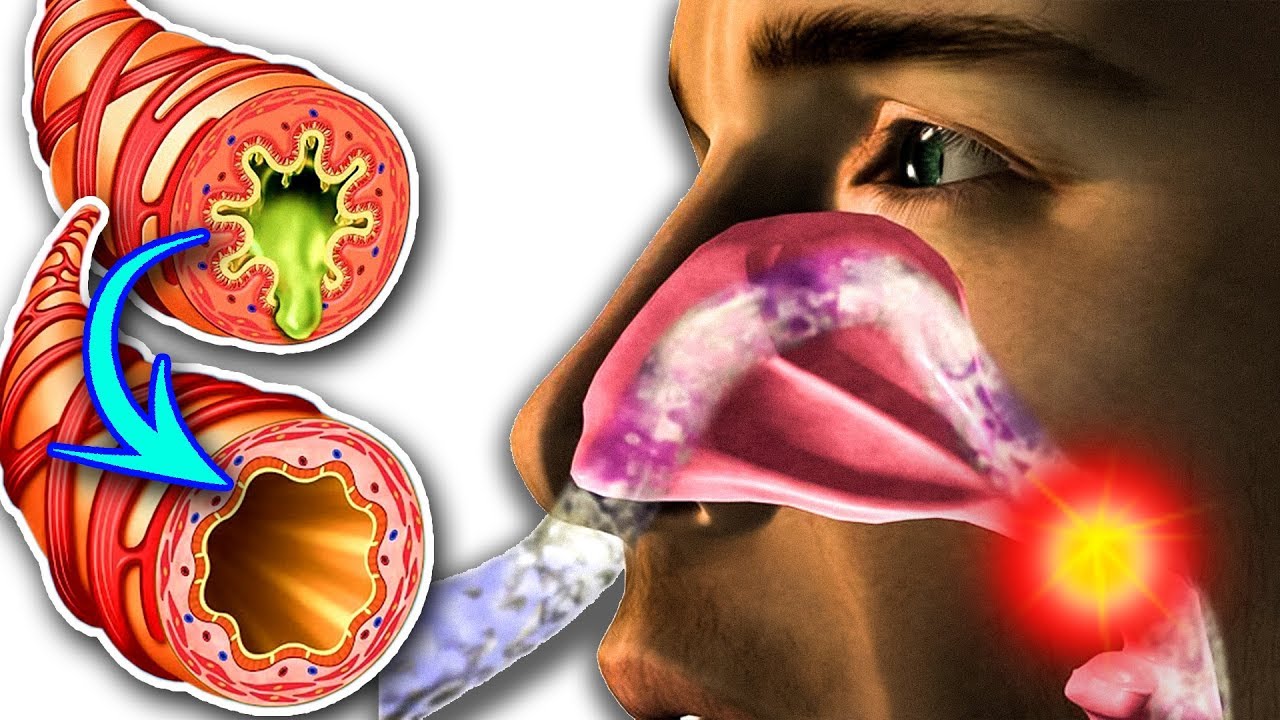

Симптомы и причины скопления воды в легких